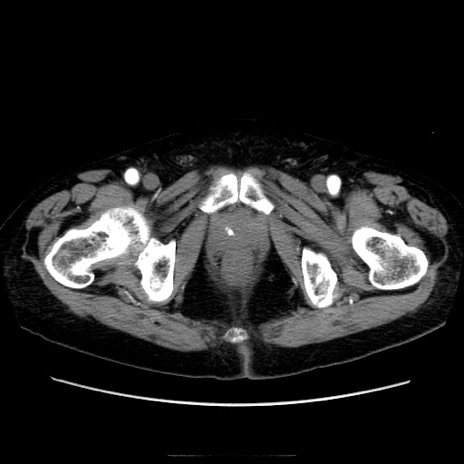

症例21(横断像)

【症例】70歳代男性

【主訴】腹痛

【現病歴】肝硬変・肝細胞癌にてかかりつけの方。約9時間前に食後より腹痛出現。症状が徐々に増悪し、嘔吐出現したため来院。

【既往歴】肝硬変、肝細胞癌(RFA、TACE後)

【身体所見】意識清明、表情苦悶様、BT 36℃、BP 129/78mmHg、P 88bpm、SpO2 97%(RA)、右上腹部から心窩部にかけて圧痛あり、反跳痛なし、筋性防御あり。

【データ】WBC 5800、CRP 0.16